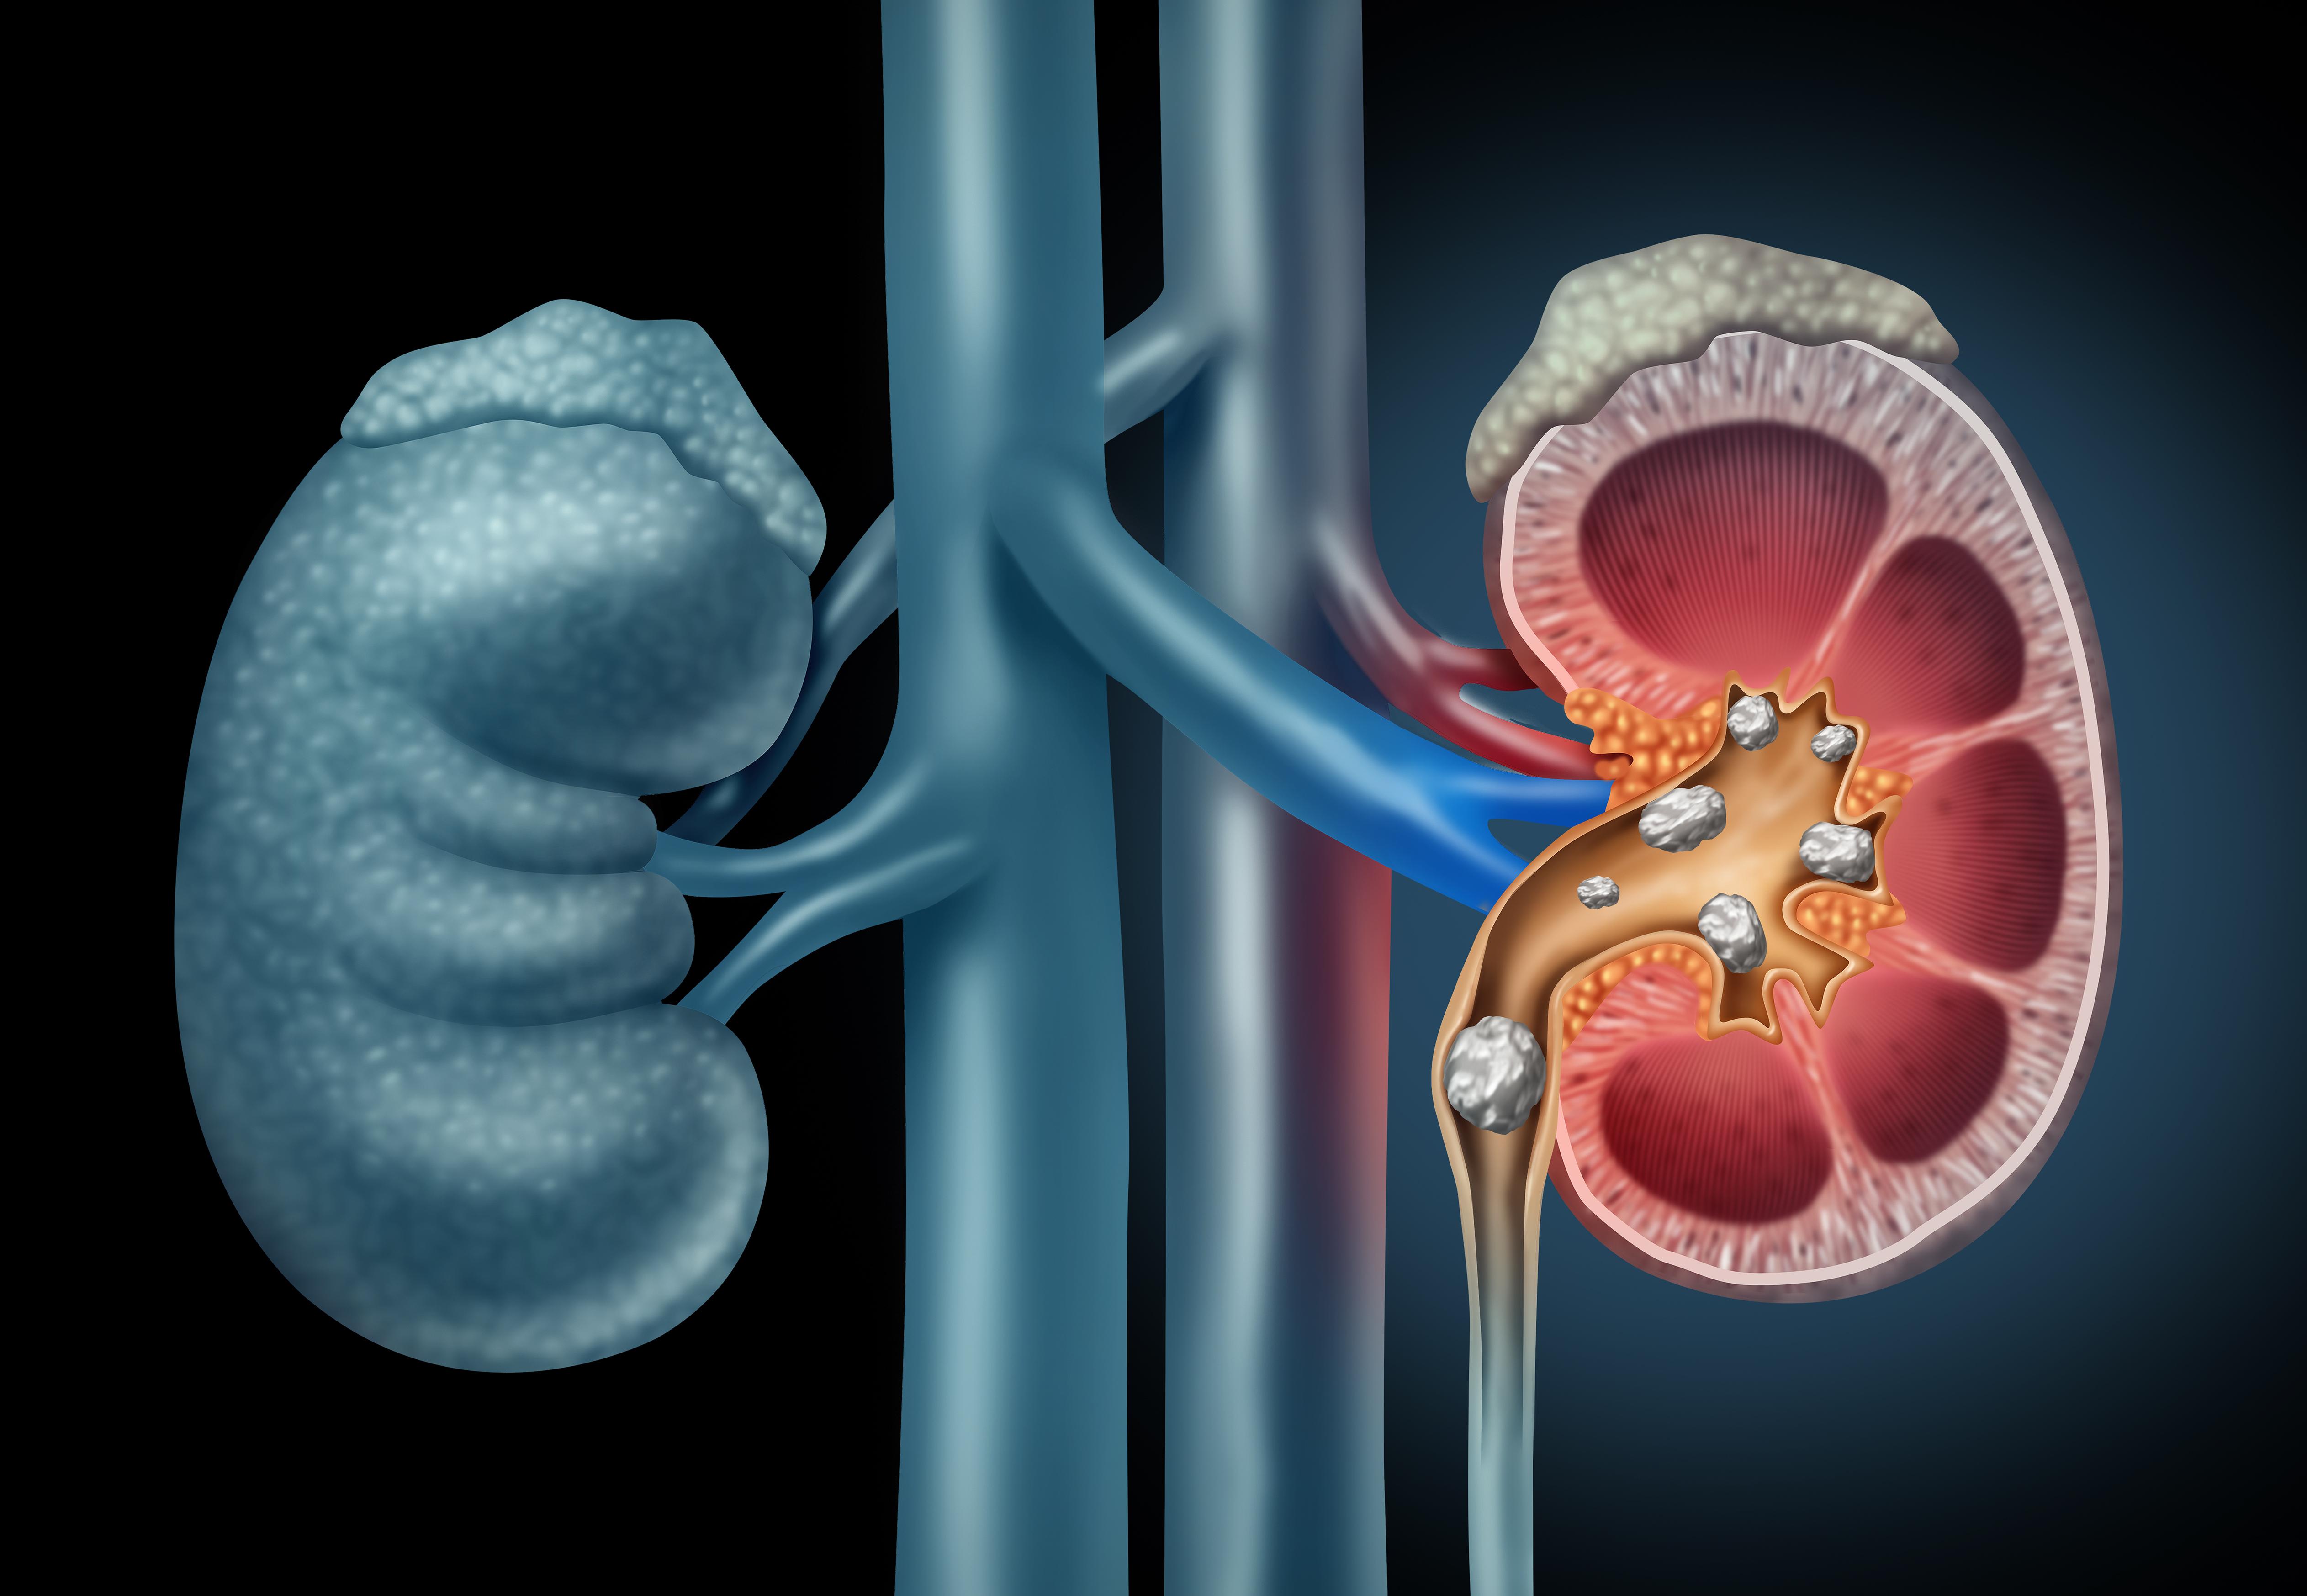

Calculii renali sunt depozite solide formate din minerale și săruri care se pot dezvolta în sistemul urinar. Ele rezultă din cristalizarea unor substanțe prezente în urină și pot varia ca mărime, structură și compoziție, de la granule foarte mici până la mase care pot obstrucționa fluxul urinar. Tipurile frecvente includ calculi pe bază de calciu, acid uric, struvit sau cistin, fiecare având mecanisme de formare și factori predispozanți ușor diferiți.

Formarea calculilor poate fi influențată de factori precum volumul redus de urină, modificări ale compoziției urinare sau anumite condiții metabolice; acești factori pot contribui la creșterea concentrației unor substanțe care favorizează cristalizarea. În multe cazuri, prezența unui calcul poate determina durere sau alte simptome care pot necesita evaluare și management medical adecvat, iar strategiile preventive sau terapeutice sunt adaptate în funcție de tipul și severitatea problemei.

Formarea calculilor apare în general când urina devine supersaturată cu substanțe care cristalizează; condiții care modifică compoziția urinei pot favoriza acest proces. Tipuri frecvente includ calculi pe bază de calciu (de obicei oxalat sau fosfat), acid uric, struvit sau cistină, iar fiecare tip are mecanisme metabolice ușor diferite care pot contribui la formare. Anumite tulburări metabolice, precum și unele medicamente sau intervenții chirurgicale, pot influența echilibrul electroliților sau pH-ul urinei și astfel pot crește predispoziția la pietre.

Factorii care pot crește riscul includ în mod frecvent consumul insuficient de lichide, dietă bogată în sodiu sau în proteine animale, aport crescut de oxalați alimentari și condiții metabolice asociate cu excesul de calciu sau acid uric în urină; obezitatea, istoricul familial și anumite anomalii anatomice ale tractului urinar pot, de asemenea, să joace un rol. Infecțiile urinare recurente pot favoriza apariția calculilor de tip struvit. Pentru resurse suplimentare privind prevenția și cauzele specifice, consultați informații despre calculi renali.